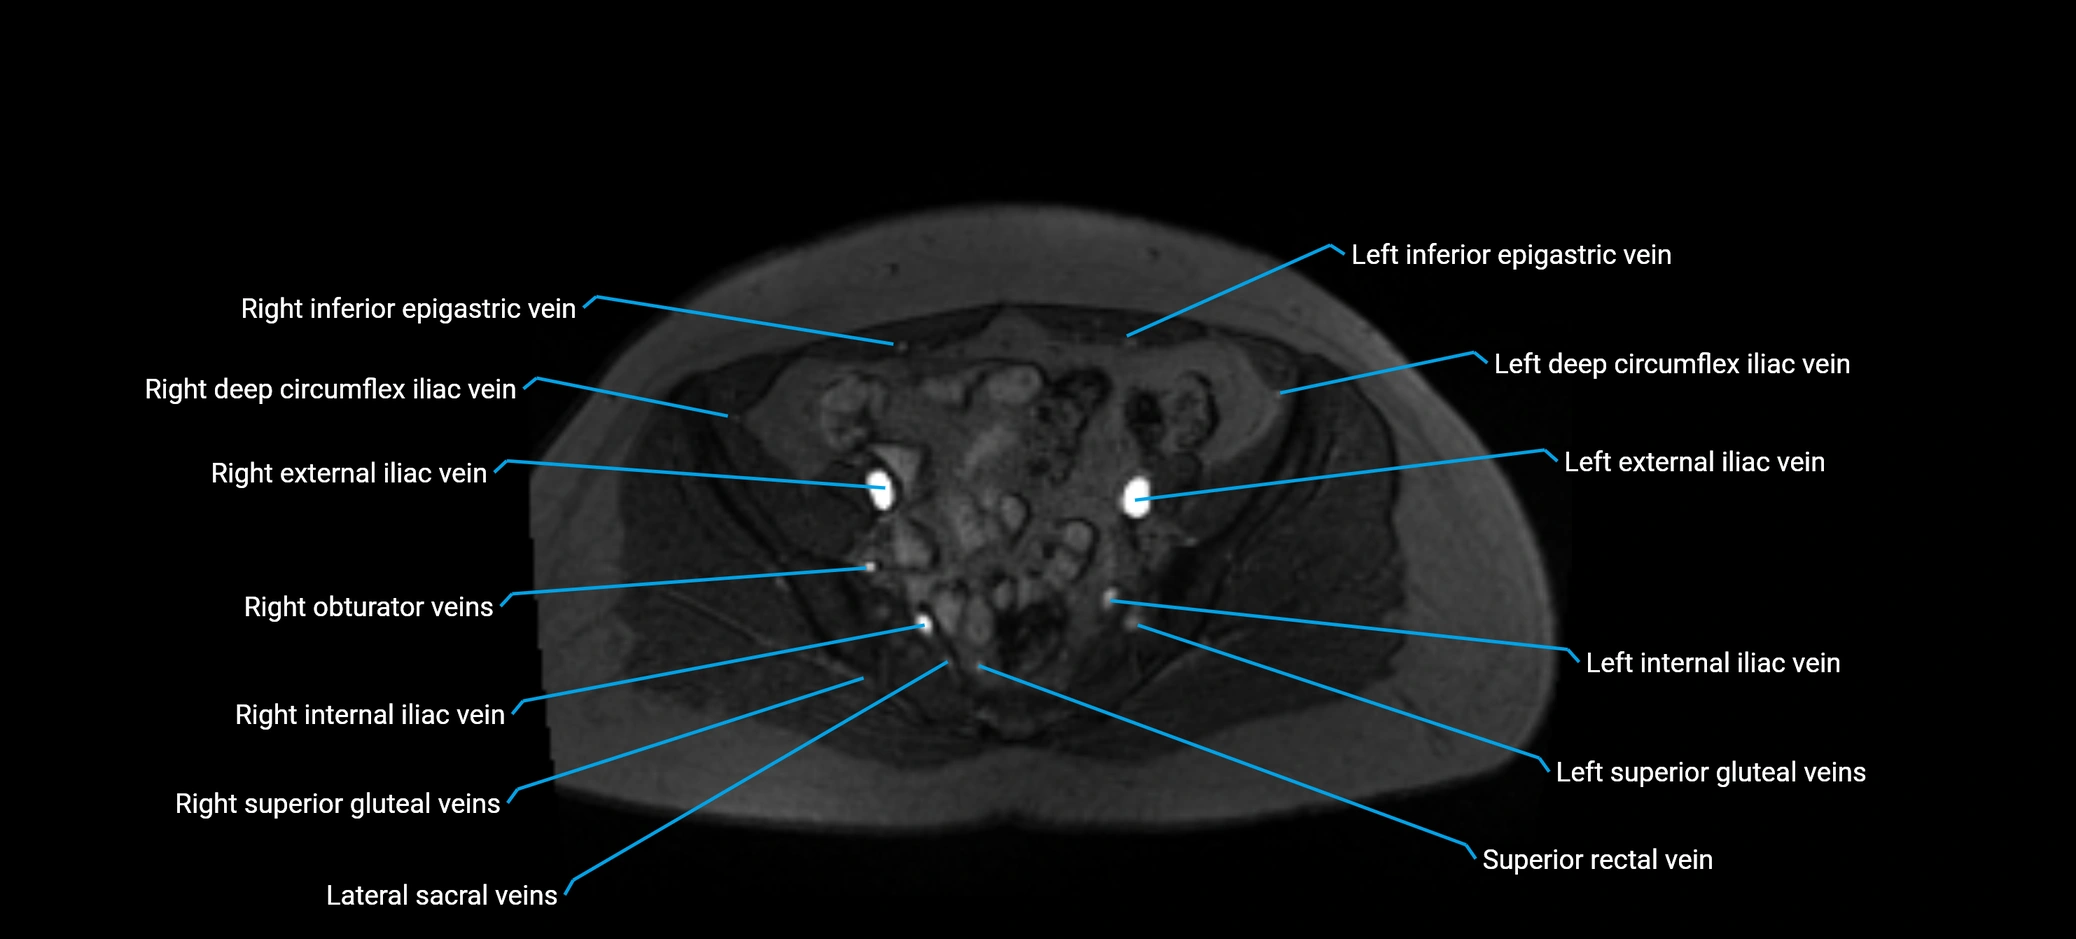

MRI image

image